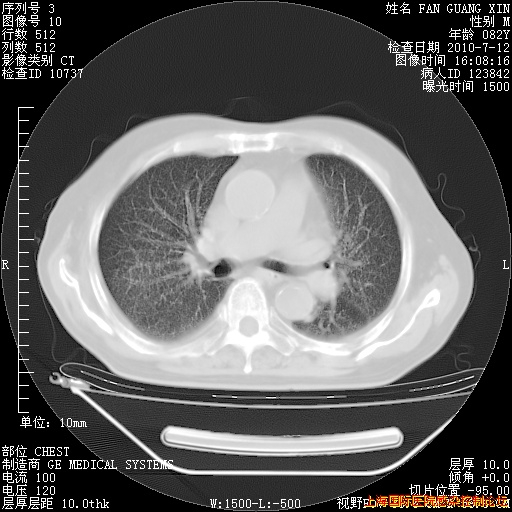

今天复查CT

今天CT

整整相隔30天的肺部CT好像有所好转啊。甲强龙减量第3天,需要观察体温。

海管,自昨日你和我通完话后,不知您岳父消化道症状有无缓解?体温怎样?阅读7.12日胸部ct,个人认为目前激素治疗是有效的,甲强龙减量是适宜的。因在抗痨治疗,需密切观察肝功、肾功能和血常规。不过,老年、长期住院和大量使用激素,很担心菌群失调发生